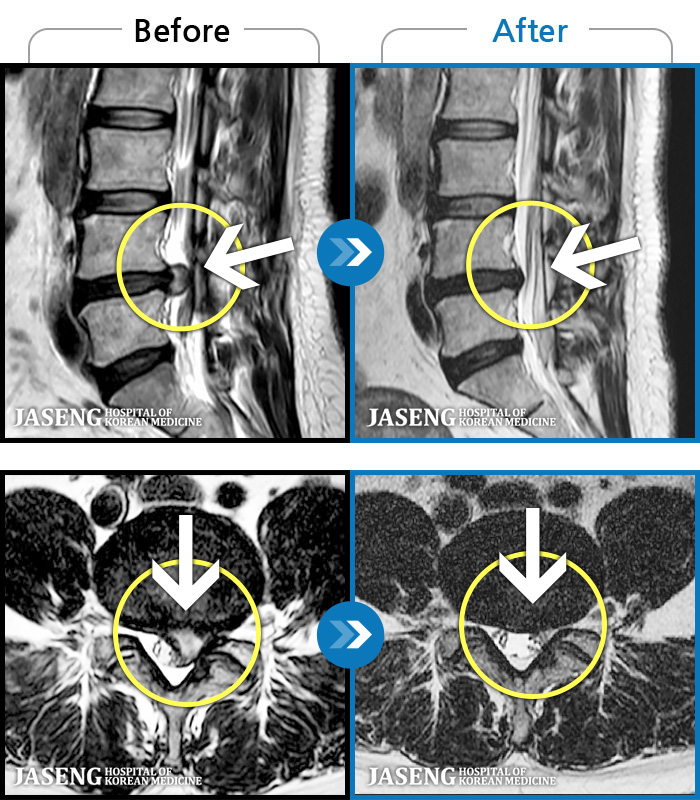

MRI로 보는 치료결과

1,228건의 MRI 전후 사진으로 터진 디스크 흡수 사례를 확인하세요.

[해운대] 23.09.18~25.01.27

※ 환자분에게 사전 동의를 받아 동일 조건에서 촬영되었으며, 개인에 따라 치료 후 부작용이 발생할 수도 있으니 사전에 의료진과 상담 후 치료를 진행하시기 바랍니다.